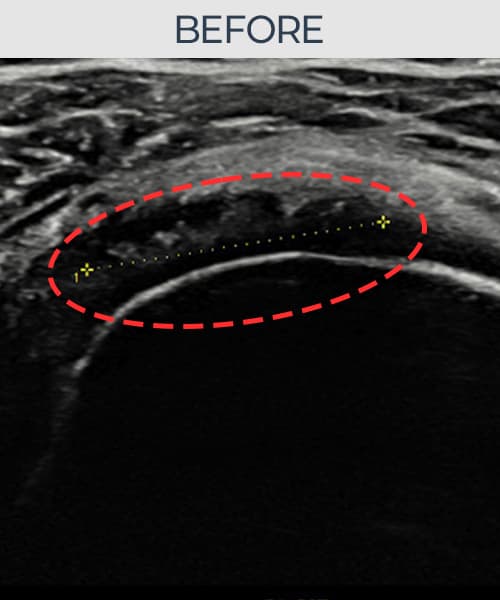

実際の患者様の施術前後の超音波画像。

手術なしで実現できる回復をご確認ください。

[経過期間: 24.07.10~24.09.18]

[縫縮術] 超音波検査にて右 棘上筋腱 関節面側断裂進行型(12mm × 7mm (腱厚の約55%欠損))を確認。縫縮術施行後、腱の連続性が回復し、日常生活に復帰されました。